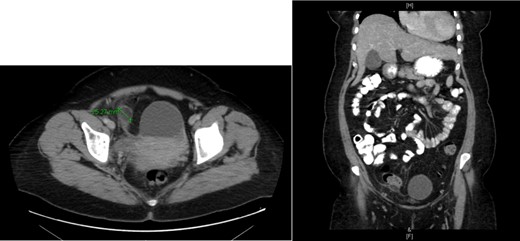

Upon reviewing her laboratory investigations, C-reactive protein was the only elevated parameter of 18.51 mg/l. All other routine laboratory were within normal range. She underwent a CT abdomen/pelvis, which showed an oval shaped well-defined fatty texture at right lower quadrant measuring 2.8 × 2.4 cm with fat stranding that was suggestive of an epiploic appendagitis (Fig. 1). The CT also noted a large well-defined cyst with a single septum suggestive of left adnexal cyst. A pelvic ultrasound examination showed a cystic structure measuring 6 × 6 cm in left ovary with normal color flow doppler seen.